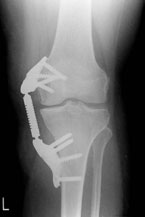

In den letzten 15 Jahren ist das Konzept der so genannten Umstellungsosteotomie entscheidend weiterentwickelt worden, sodass dieses Knorpeloperations-Verfahren seinen Schrecken verloren hat. Das Vorgehen ist in diesem Fall folgendermaßen: Es wird zunächst eine genaue Diagnostik mittels Röntgen vorgenommen, diese erfolgt mit Hilfe einer so genannten Achsaufnahme des gesamten Beines im Stand. Anhand dieser Aufnahme wird die Fehlstellung sowohl innen oder außen am Kniegelenk genau ausgemessen. Dann wird ausgemessen, wie durch ein kleines aufbiegendes Verfahren am Schienbeinkopf (häufigste Vorgehensweise) oder durch eine Einkerbung des Oberschenkelknochens (selteneres Verfahren) die Achse entsprechend der Stelle, an der die Verschiebung am Bein vorhanden ist, bei der Knorpeloperation wieder korrigiert werden kann. Durch neu entwickelte Instrumente handelt es sich dabei nicht mehr um ein Verfahren, wo der Knochen zum Beispiel am Schienbein komplett durchgeschnitten werden muss, sondern es erfolgt mehr oder minder eine Einkerbung des Knochens und der Knochen wird etwas aufgebogen. Damit der Knochen sich nicht sofort wieder verschließt, wird eine kleine Metallplatte angebracht, die den Knochen offen hält.

Aus dem Knochenmark kommen Zellen, die in der Lage sind, neuen Knochen zu bilden und so verknöchert dieser nun in der richtigen Position. Etwa 2 Tage nach der Knorpeloperation kann der Patient aus dem Krankenhaus entlassen werden, eine Teilbelastung an Gehhilfen von ca. 3 bis 6 Wochen ist notwendig bis der Knochen genügend Stabilität bekommen hat.

Dieses Verfahren ist ausgesprochen wirkungsvoll. Selbst wenn ein Kniegelenksknorpelschaden nicht komplett regeneriert, wird doch durch die Gewichtsumverteilung der Schmerz meist vollkommen beseitigt und es bildet sich in sehr vielen Fällen eine Knorpelregenerationsschicht. Dieses Verfahren kann auch mit weiteren Knorpelverfahren kombiniert werden. Somit können auch bei schweren Kniegelenksknorpelschäden auf biologische Art Erfolge erzielt werden.